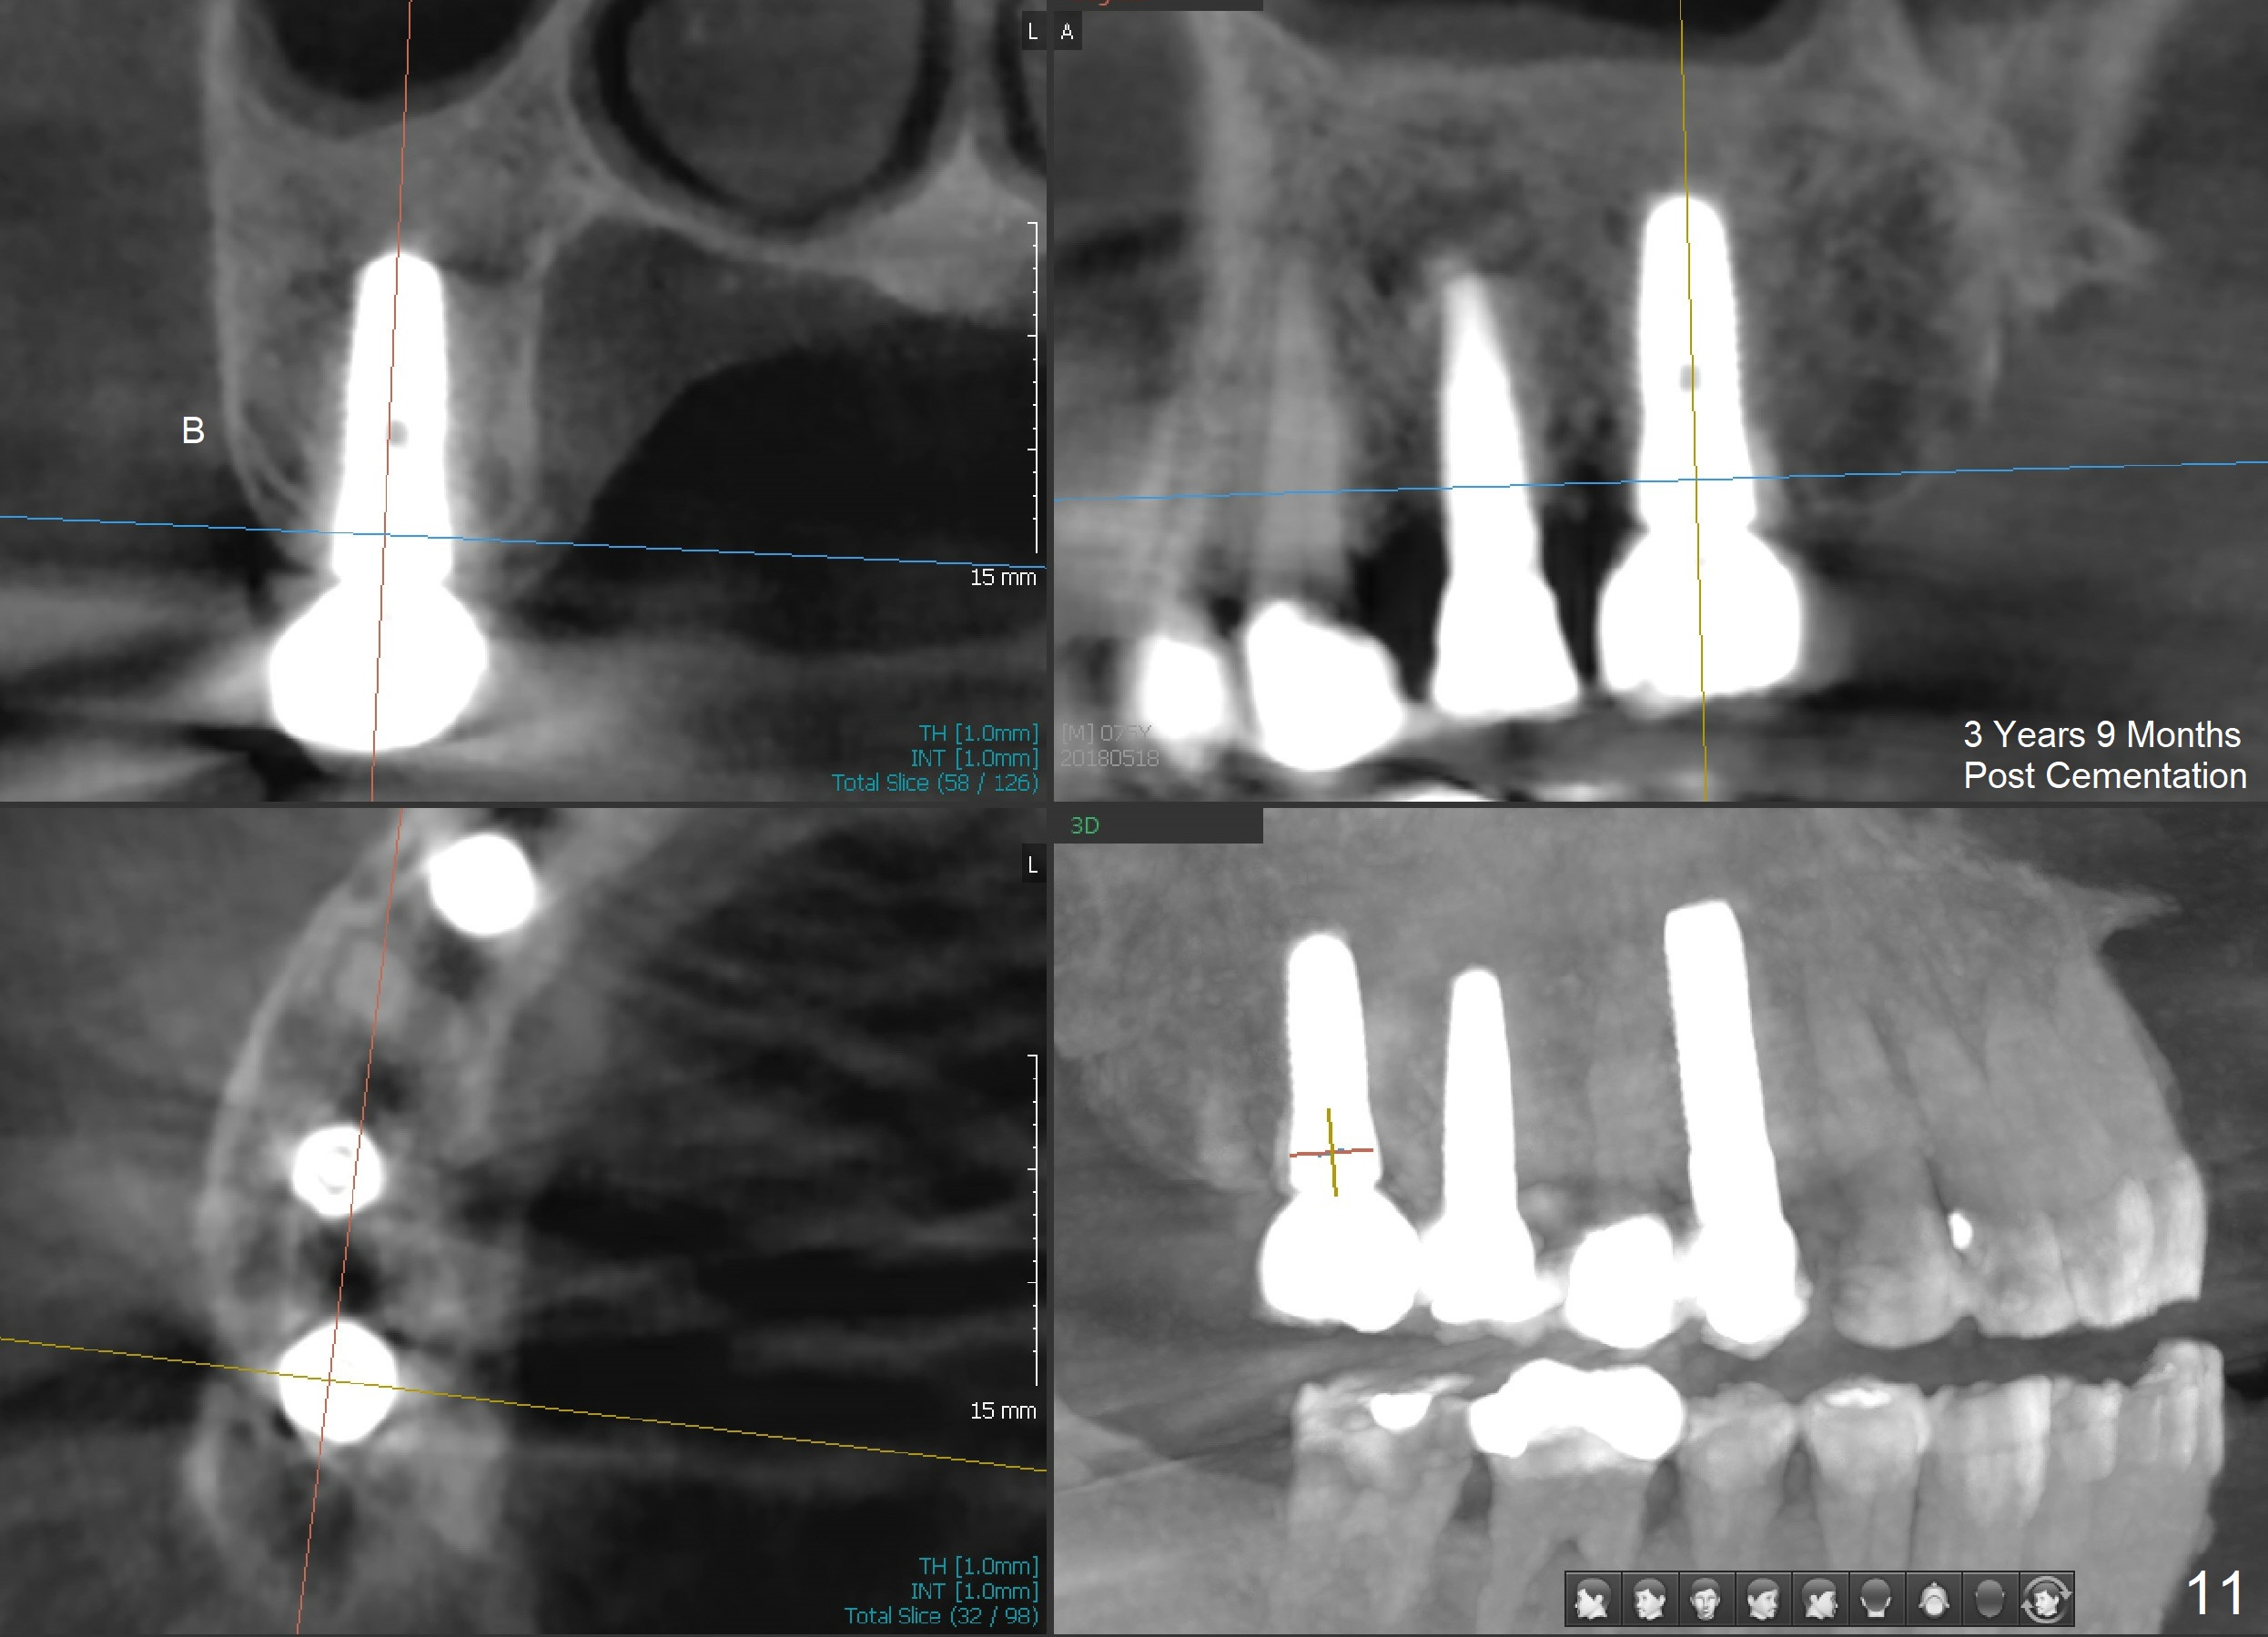

Analysis of preop PA suggests that the density of the cancellous bone is low at the site of the tooth #2. It is confirmed when a 2 mm pilot drill is used to initiate osteotomy. There is no drilling resistance once the pilot drill penetrates the cortex. A parallel pin is inserted for trajectory (Fig.1: P; 8 mm deep). The osteotomy is slightly moved distally with Lindermann bur and enlarged by inserting Bone Expanders from 2.6 to 3.8 mm at the depth of 12 mm (Fig.2). The osteotomy is then intended to move mesially and the depth is increased to 14 mm. Finally a 5.3x14 mm submerged implant is placed with insertion torque ~ 40 Ncm (Fig.3). The implant looks to have been tightly engaged into the bone (Fig.4). In one word, minimal bone removal is required for implant placement in the soft bone, particularly in the maxillary posterior region. A 8.2 mm healing abutment is placed; the flaps are closed by Chromic gut suture and perio glue (Fig.5). The wound heals normally 1 week postop (Fig.6). Fig.7 shows X-ray 3 months postop (H: healing abutment). Soft tissue looks healthy 4 months postop before (Fig.8) and after (Fig.9) removal of the healing abutment for restoration. There is no bone loss 7 months post cementation and 11 months postop (Fig.10 C: crown). It appears that bone expansion prevents bone resorption. There is no bone resorption 1 year 9 months post cementation. The implant is functioning 3 years 9 months post cementation (Fig.11).